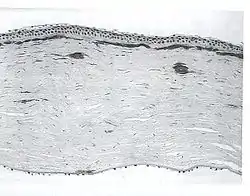

| A network of thick linear corneal opacities in patient with a variant of LCD1 (LCD type III) due to a homozygous p. Leu527Arg mutation in the TGFBI gene | |

Lattice dystrophy gets its name from an accumulation of amyloid deposits, or abnormal protein fibers, throughout the middle and anterior stroma.

Filamentous opacities appear in the cornea with intertwining delicate branching processes. During an eye examination, the doctor sees these deposits in the stroma as clear, comma-shaped overlapping dots and branching filaments, creating a lattice effect. Over time, the lattice lines will grow opaque and involve more of the stroma. They will also gradually converge, giving the cornea a cloudiness that may also reduce vision. The disease is bilateral, usually noted before the end of the first decade of life. Although lattice dystrophy can occur at any time in life, the condition usually arises in children between the ages of two and seven.

In the examination of biomicroscopy, it appears as branches spread on the corneal stroma in the appearance of ghost vessels. diagnosis can also be confirmed with anterior segment OCT (visante OCT ,spetral domain OCT).The interwoven linear opaque filaments have some resemblance to NERVES, but may not be observed in all affected members of families with the condition. Recurrent corneal erosions may precede the corneal opacities and even appear in individuals lacking recognizable stromal disease. Amyloid deposits are found throughout the corneal stroma. Linear and other shaped opaque areas accumulate particularly within the central corneal stroma, while the peripheral cornea remains relatively transparent.